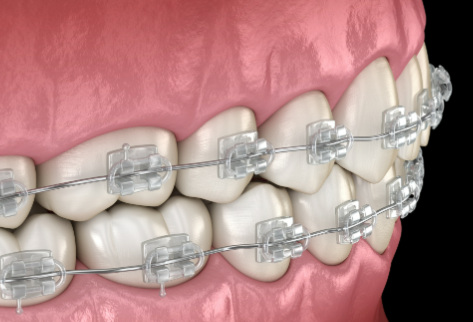

牙齿美容整形多少钱?2026年最新价格揭秘与注意事项! 本文围绕2026年牙齿美容整形价格及注意事项展开。牙齿整形费用参考范围8000 - 30000元,受畸形程度、地区、矫治器材料等因素影响。不同矫治器材料费用有别,国产亲民、进口稍贵、隐形更贵。还介绍了医院医生、治疗方案等影响价格的其他因素。同时给出选择正规机构、与医生沟通等注意事项,助大家选合适方案美牙。 牙齿美白 2026年03月04日 0 点赞 0 评论 7 浏览